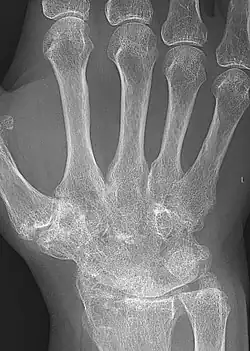

| A hand severely affected by rheumatoid arthritis. This degree of swelling and deformation does not typically occur with current treatment. | |

X-rays of the hands and feet are generally performed when many joints are affected. In RA, there may be no changes in the early stages of the disease, or the X-ray may show osteopenia near the joint, soft tissue swelling, and a smaller than normal joint space. As the disease advances, there may be bony erosions and subluxation. Other medical imaging techniques such as magnetic resonance imaging (MRI) and ultrasound are also used in RA.[20][79]